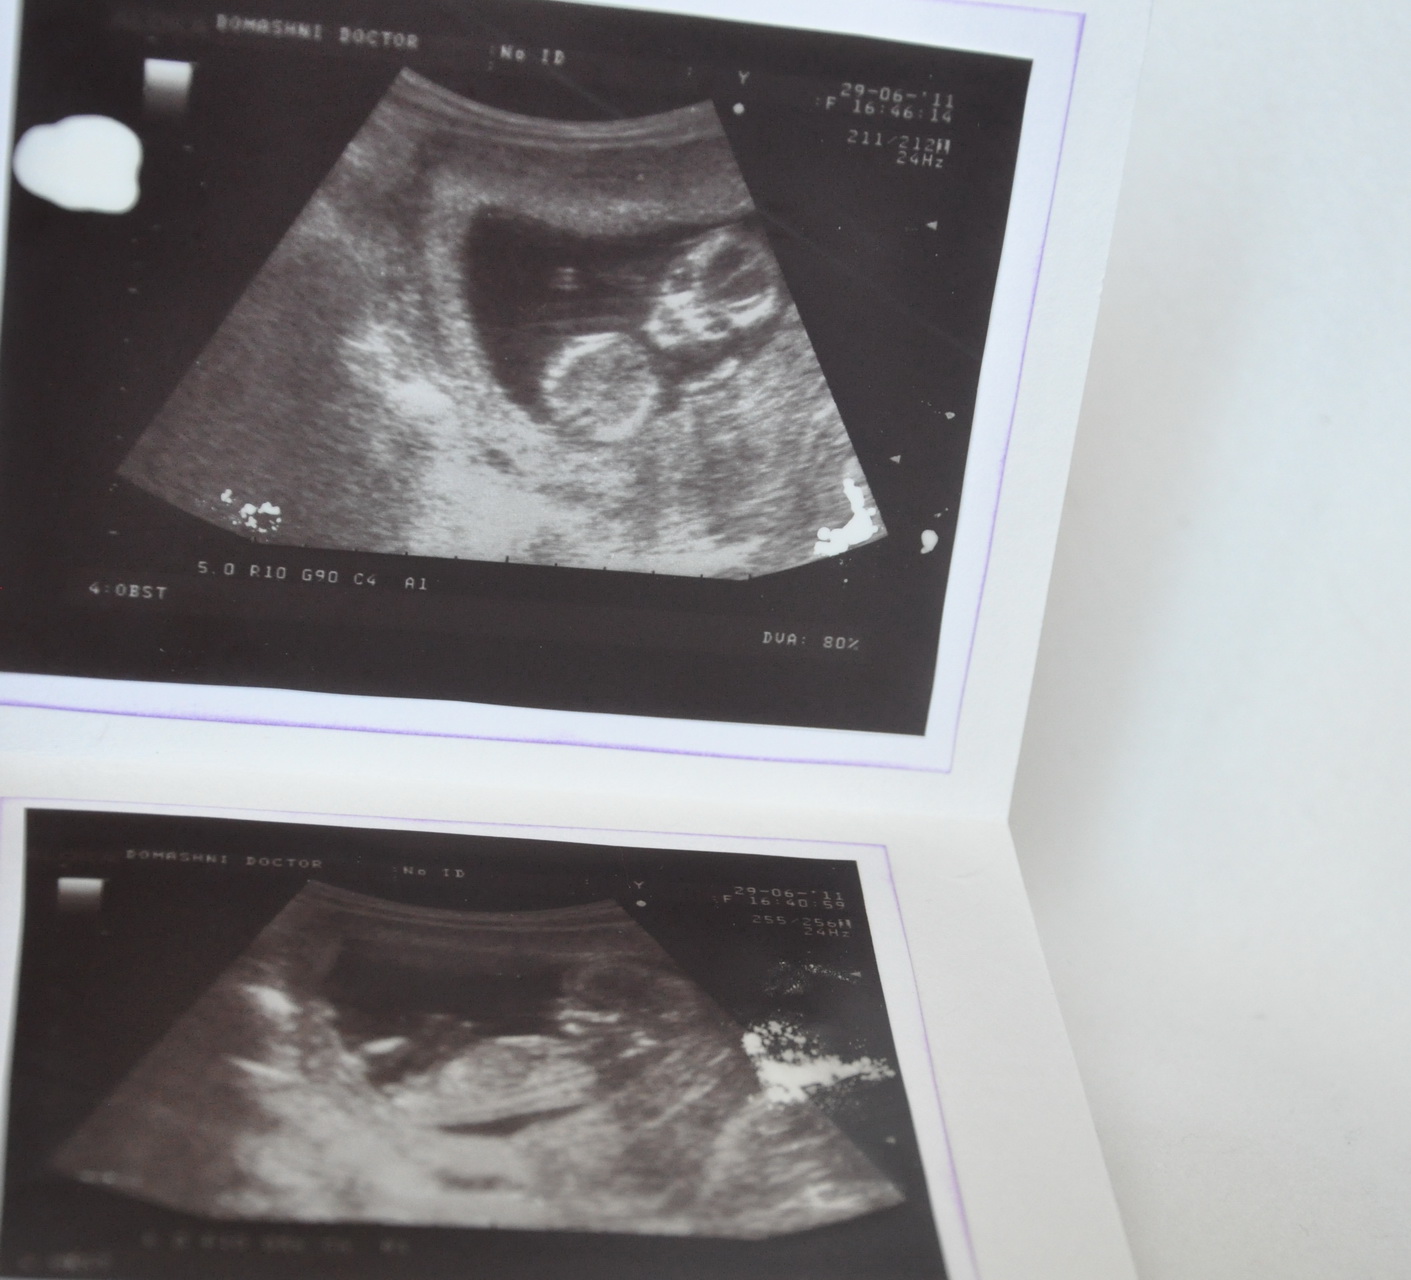

Ультразвуковое исследование (УЗИ) является одним из наиболее распространенных методов диагностики в медицине. Во время УЗИ врач использует специальный аппарат, называемый ультразвуковым сканером, чтобы создать изображение внутренних органов и тканей пациента.

Для получения фото УЗИ пациенту обычно предлагается лечь на специальный стол в позиции, наиболее удобной для проведения исследования. Врач наносит гель на кожу в области, которую необходимо исследовать, и затем прокатывает ультразвуковую головку по поверхности кожи. Ультразвуковые волны проникают внутрь органов и тканей, отражаются от них и возвращаются обратно к ультразвуковой головке, где преобразуются в изображение на экране.

Фото УЗИ могут быть черно-белыми или цветными, в зависимости от настроек ультразвукового сканера. Они могут быть сохранены в цифровом формате для последующего анализа и диагностики.